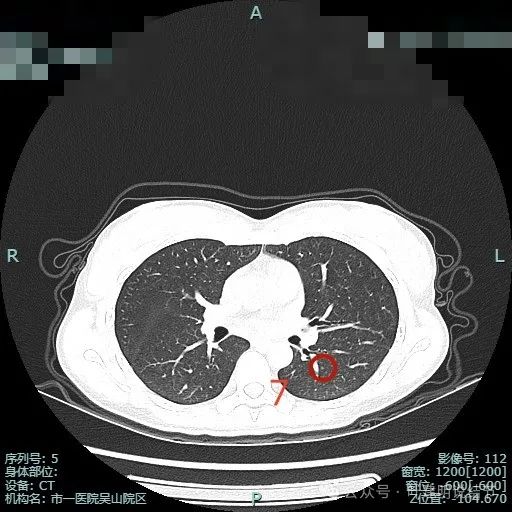

病灶7:左下叶微小淡磨玻璃结节,整体轮廓较清,考虑肺泡上皮增生或不典型增生可能。